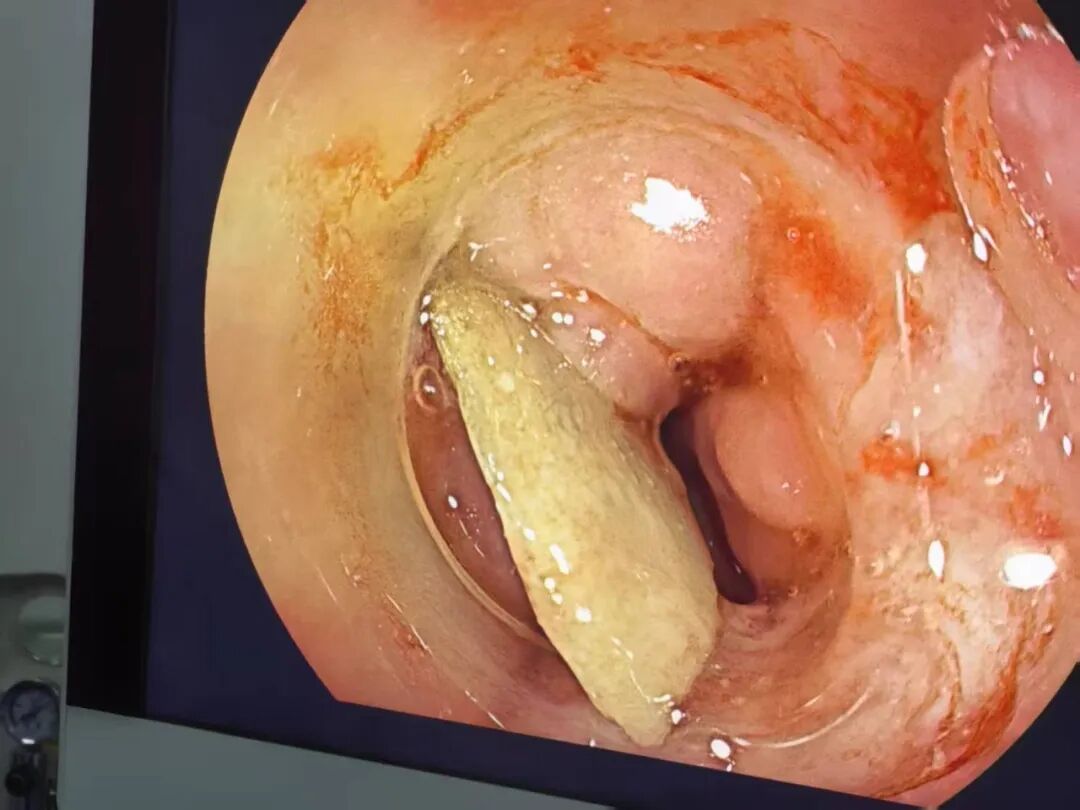

3月26日,手术在消化内科、麻醉科、呼吸与危重症医学科协作下顺利完成,术中探查发现鸡骨尖端嵌入食管中段,周围黏膜严重水肿,穿孔处可见脓性分泌物,通过密切合作,顺利取出长约3cm的尖锐骨片。